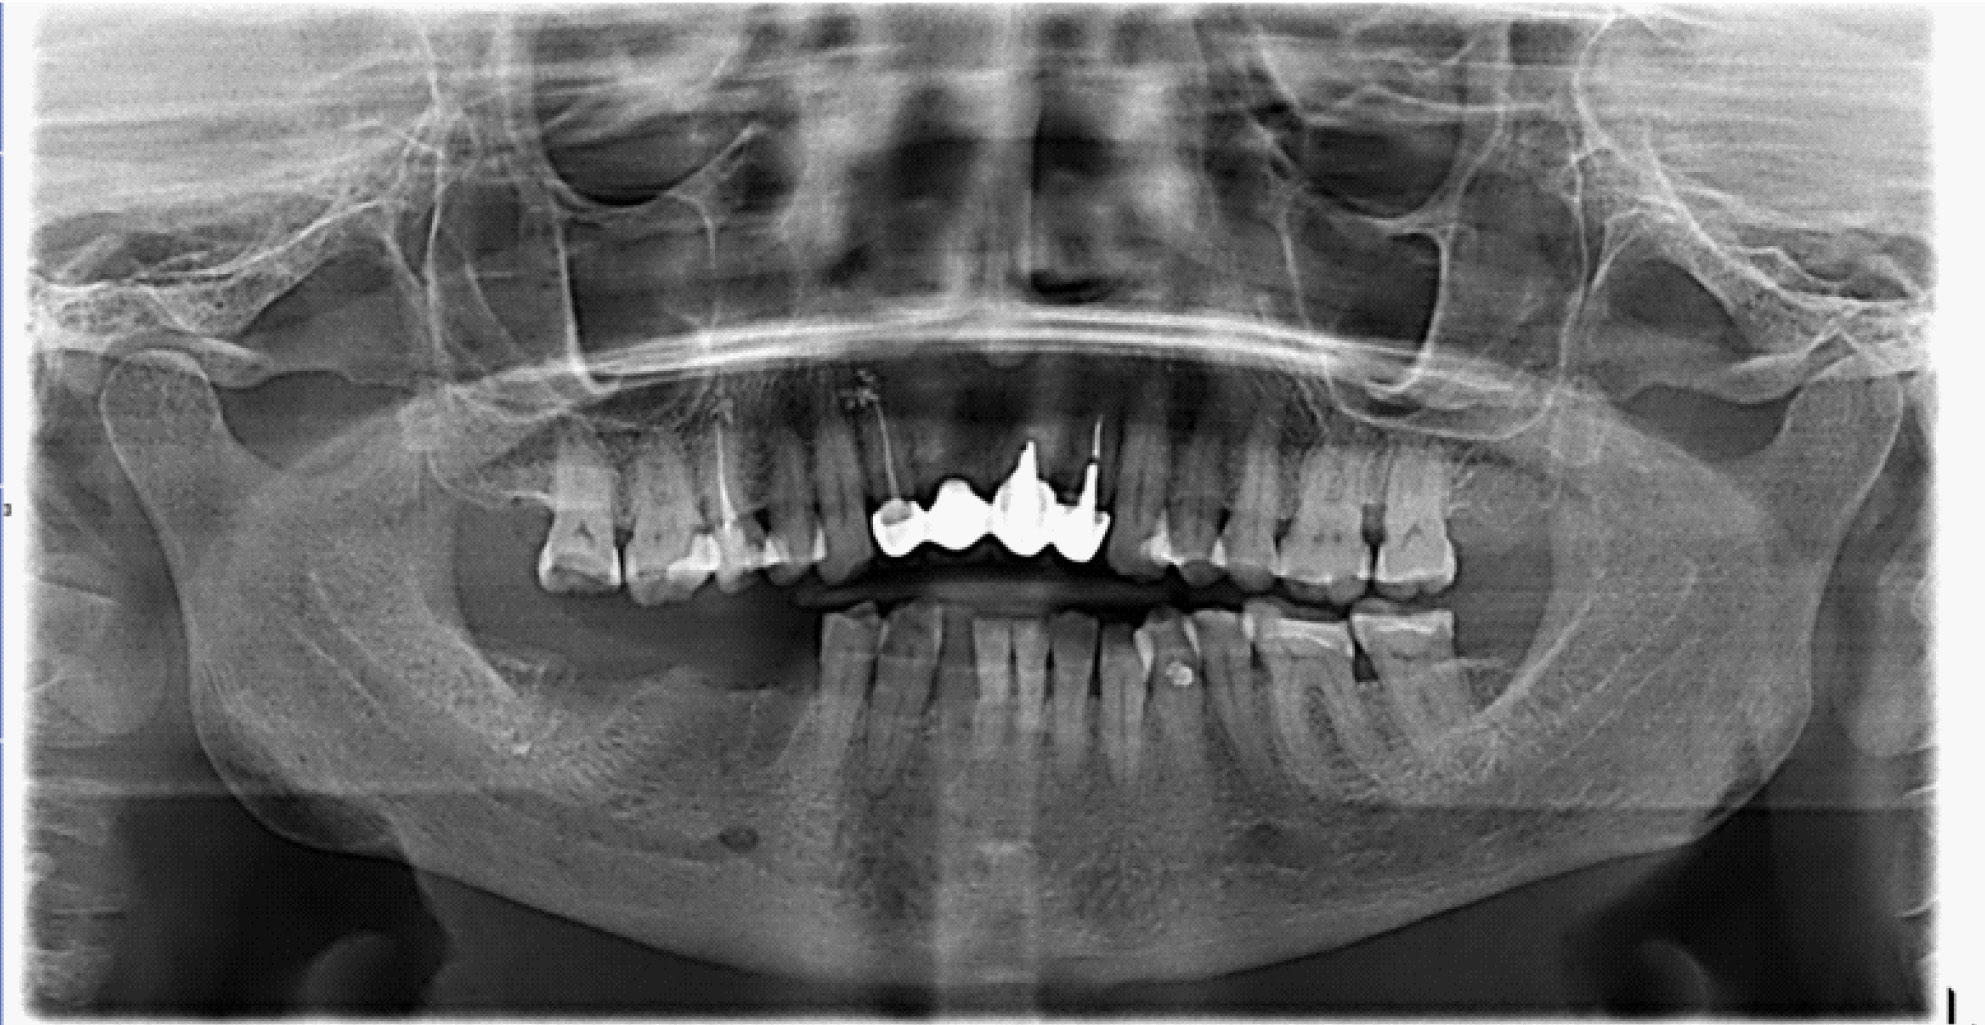

Пальпация безболезненная. На ортопантомограмме определяются лунки зубов 4.7, 4.5 без явных признаков секвестрирования (рис. 3).

Рис. 3. Ортопантомограмма на этапе лечения остеонекроза нижней челюсти справа у пациентки Б. в 2022 г.

Пациентка находилась на лечении в период с 2022 по 2024 г.

В настоящее время выделяют два основных подхода к лечению БФОНЧ, к ним относятся консервативный и хирургический подход. Выбор тактики лечения пациента зависит от стадии заболевания. Консервативное лечение предусматривает назначение пациентам курсовой антибактериальной, симптоматической терапии препаратов для улучшения микроциркуляции, ежедневной обработки очагов поражения костной ткани растворами антисептиков, частичная некроэктомия, удаление подвижных секвестров, а также тщательное соблюдение гигиены полости рта (рис. 4).

За период лечения пациентки Б. было выполнено хирургическое лечение в следующем объеме: кюретаж лунок удаленных зубов, частичная секвестрэктомия, резекция альвеолярной части нижней челюсти справа, вскрытие и дренирование гнойных очагов в стадии обострения патологического процесса. Отмечалось улучшение клинической и рентгенологической картины в полости рта (рис. 5, 6).